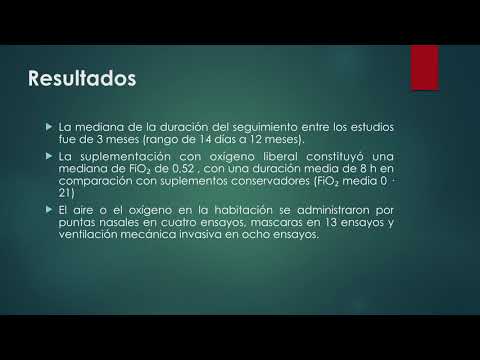

Morbimortalidad en enfermedades agudas del adulto tratadas con oxigeno liberal vs conservador. Dra. María Laura Estrella. Residencia de Cardiología. Hospital C. Argerich. Buenos Aires